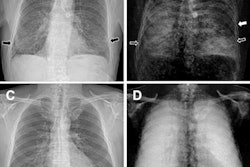

Dark-field CT reconstruction of a clinical chest phantom. Besides conventional attenuation contrast, dark-field contrast is also retrieved, providing information on the porosity of tissue. Here, the chest phantom is filled with a foam insert that simulates lung tissue, and tubes containing different materials (left-to-right: POM, air, powdered sugar, water). While purpose structures are too small and have low conventional attenuation CT, they are easily visible in the dark-field image. Image and caption courtesy of Manuel Viermetz.The group found that the device was effective in capturing dark-field data (i.e., small-angle scattering), which "provides additional valuable diagnostic information on otherwise unresolved tissue microstructure," it noted.

The research lays a foundation for implementing dark-field CT for real-world medical applications, according to the authors. In fact, once dark-field CT systems were approved for clinical use, the group would expect that they would have "immediate impact" on lung imaging, as the technique has already shown promise in small animal studies on chronic obstructive pulmonary disease, emphysema, fibrosis, and lung cancer.